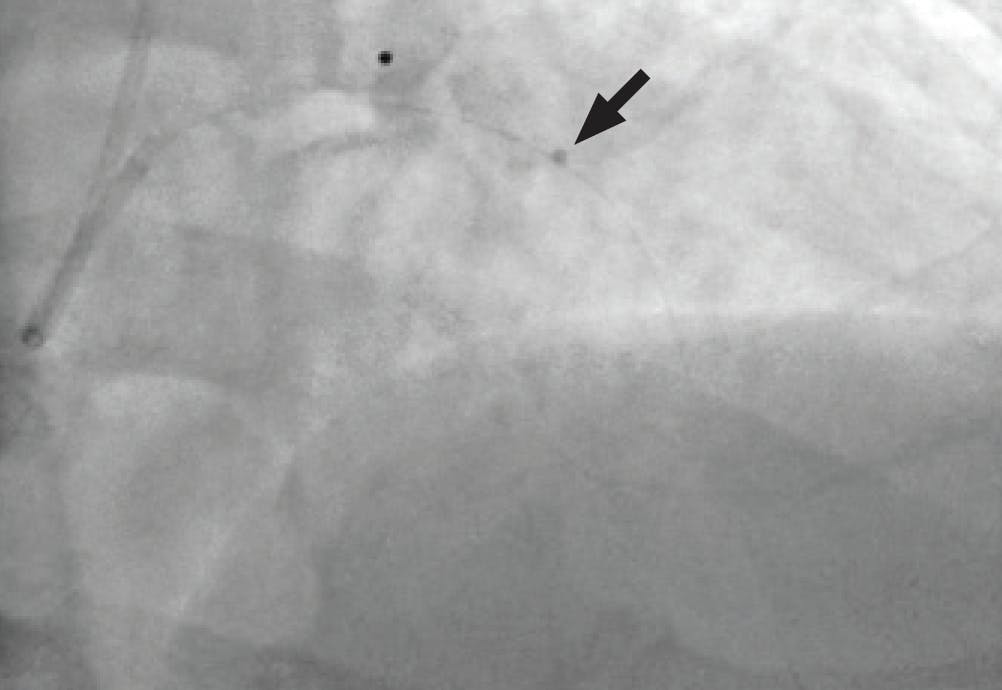

After achieving wire access, the Lightning Flash 2.0 was inserted. While in “Gallop Mode,” the saddle clot burden and subsequently the left and right main PAs were aspirated. Once the algorithm returned to “Sampling Mode,” aspiration was turned off and angiograms were obtained to assess the progress. After 5 minutes of aspiration, reperfusion of the main PAs and distal branches was achieved (Figure 3, Figure 4, and Figure 5), with improvement in the patient’s vital signs and no device-related complications.

Figure 5. Thrombus removed.